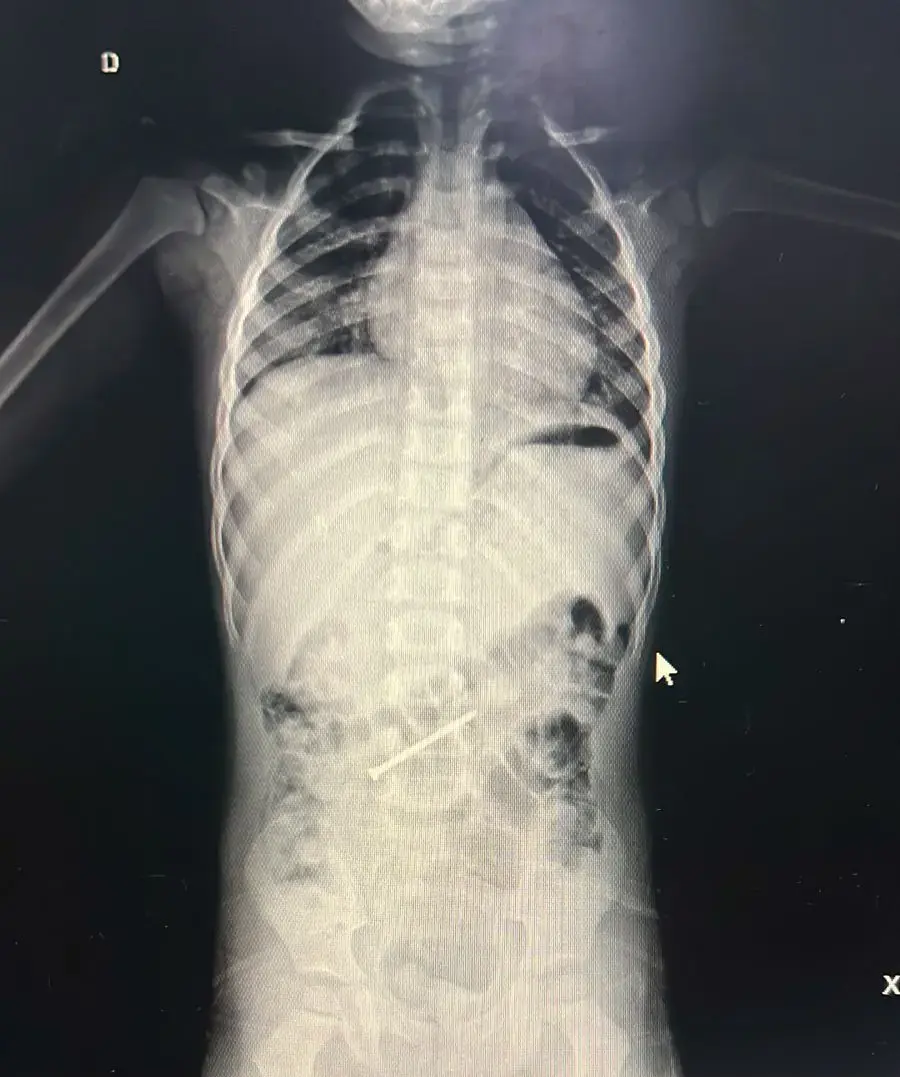

Um menino de 3 anos está internado no Hospital do Juruá, em Cruzeiro do Sul, após ingerir um prego que ficou alojado no intestino. A criança, moradora do município de Ipixuna, no Amazonas, deu entrada na unidade hospitalar na quarta-feira, 14, cerca de seis dias depois do ocorrido.

A retirada do objeto está prevista para a tarde desta quinta-feira, por meio de uma colonoscopia, também chamada de endoscopia digestiva baixa. O procedimento permite acessar o intestino grosso para localizar e remover o prego de forma menos invasiva.

“Será feita uma colonoscopia para a retirada do prego que está no intestino grosso. A criança está passando pelo preparo, que consiste na limpeza intestinal, para que possamos realizar o procedimento com segurança”, explicou o médico.